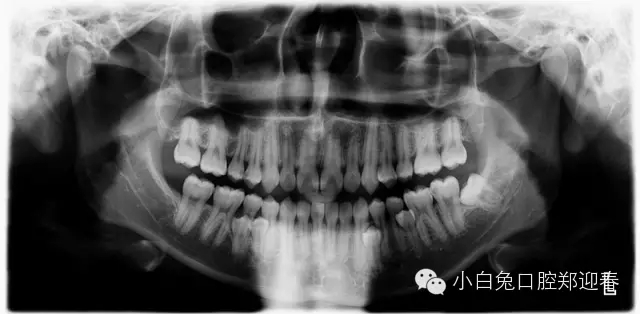

“多生牙”案例集錦(鄭穎春)......

額外牙可發(fā)生于乳牙列,也可發(fā)生于恒牙列,但恒牙列發(fā)生率多于乳牙列。額外牙經(jīng)常在上頜出現(xiàn),上、下頜出現(xiàn)比例為10∶1,可單個或多個、單側(cè)或雙側(cè)出現(xiàn),形態(tài)可同正常牙,也可是畸形牙、過小牙。